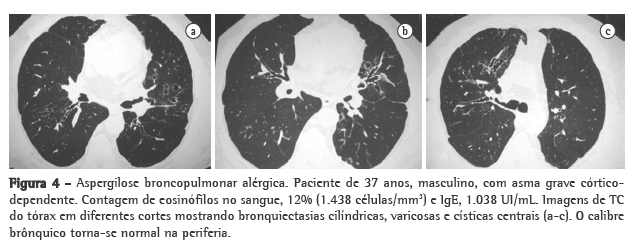

As bronquiectasias centrais são quase patognomônicas para a ABPA, desde que fibrose cística e deficiência de alfa-1 antitripsina tenham sido afastadas. Em um estudo que avaliou a TC de 17 pacientes com ABPA e de 11 pacientes asmáticos com teste cutâneo positivo para Aspergillus sp., mas sem evidências de ABPA, bronquiectasias foram encontradas em 14/17 pacientes e em apenas 2/11, respectivamente.(40) Quase a totalidade das bronquiectasias encontradas na ABPA era de distribuição central. O estudo confirma a bronquiectasia central como um critério diagnóstico importante, pois esse não é um achado frequente em pacientes com asma sem ABPA. Pacientes com asma, quando apropriadamente investigados, podem apresentar algum grau de bronquiectasia cilíndrica focal e localizada, restrita a um ou no máximo dois lobos.(36) Em outro estudo, que incluiu 126 pacientes com ABPA, bronquiectasia central foi encontrada em 73% dos pacientes, e os 27% restantes tinham a doença classificada como ABPA soropositiva, ou seja, asma com teste cutâneo e sorologia contra o Aspergillus sp. positivos, mas sem ­bronquiectasias centrais.(41) A bronquiectasia central é definida quando é demonstrada nos 2/3 mediais, e o calibre brônquico normaliza-se na periferia.(36) Elas podem ser cilíndricas, varicosas ou císticas (Figura 4). Uma extensão à periferia pode ocorrer em algumas áreas ou segmentos em até 30% dos pacientes. Opacidades em V ou em Y podem significar impactação de muco e sugerir ABPA em pacientes asmáticos.(42,43) Impactação mucoide de alta atenuação é definida quando a densidade do muco for maior que a do músculo ­esquelético.

(41,44) Essa é também patognomônica da ABPA e foi notada em 29/155 pacientes (18,7%).(44) É atribuída à presença de sais de cálcio, metais (ferro e manganês) e/ou produtos de hemorragia no muco impactado. É a mesma base do achado de sinusite fúngica. Infiltrados pulmonares, com focos de consolidação, em pacientes asmáticos levantam a possibilidade de ABPA.